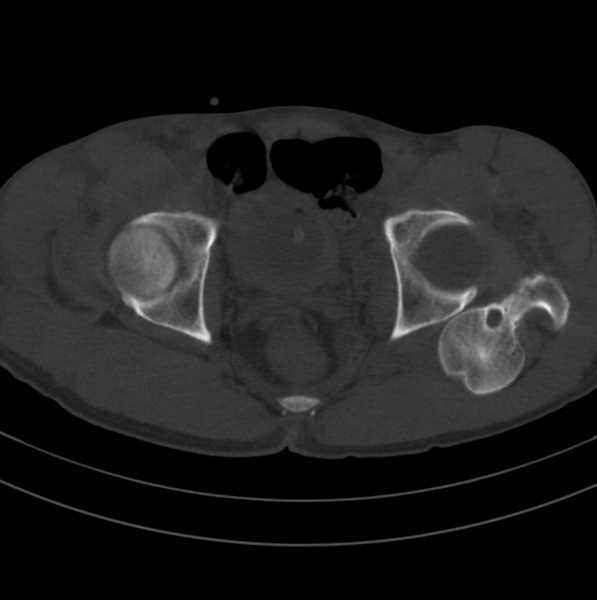

标题: CT18589:股骨头囊状阴影怎么下结论?

男、53

股骨头内的囊状阴影怎么下结论?

1.左髋后脱位。

髋关节脱位、股骨头疝窝。

左侧髋关节后脱位;左侧股骨头疝窝。

左侧髋关节后脱位、左侧股骨颈疝窝。

股骨颈疝窝是发生于股骨头基底和股骨颈的一种较少见的良性病变。发病率约在4% 一5% ,好发于中老年人,多无明显症状,常因其他病变检查时偶然发现 。病变多单侧发生,少数为双侧。影像学的正确诊断,可避免不必要的外科手术。

股骨颈疝窝系股骨颈反应区(reaction area)的纤维结缔组织和(或)液体在前部关节囊、髂股韧带及髂腰肌(腱)的机械性压迫下,通过骨皮质疝入松质骨内而形成的窝状骨质缺损 。人体站立或行走时,髋关节囊前方结构处于不断的紧张和松弛交替状态,前部关节囊(尤其是股骨颈轮匝韧带前部环绕区)和相邻的股骨头基底和股骨颈近段前外侧皮质问存在长期的压迫和相互摩擦,使邻近覆盖的滑膜组织可能因受刺激致纤维软骨化生而形成纤维结缔组织和新生软骨,相互摩擦致皮质反应性成骨,后3者成分和其内的液体共同组成了股骨反应区 。

x线平片和ct上多表现为位于股骨头基底和股骨颈近段前侧皮质下、股骨颈中轴线外侧的圆形或卵圆形透亮区或软组织密度灶,边界清楚,多伴有薄层硬化缘。病灶最大径线通常<10 mm。病灶或相邻上下层面上相邻皮质大多可见与病灶相连的局限性裂隙样缺损,可作为诊断此病的特异性征象。病灶内通常为纤维结缔组织和(或)液体。内为液体时,病灶呈均匀长t1、长t2信号。纤维结缔组织和液体同时存在时,病灶于t1wi上呈低信号,t2 wi上呈不均匀高信号。